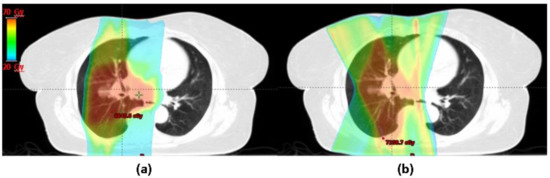

Treatment Modality: Protons vs. Photons

- Berman, A.T.; Teo, B.-K.K.; Dolney, D.; Swisher-McClure, S.; Shahnazi, K.; Both, S.; Rengan, R. An in-silico comparison of proton beam and IMRT for postoperative radiotherapy in completely resected stage IIIA non-small cell lung cancer. Radiat. Oncol. 2013, 8, 144. [Google Scholar] [CrossRef] [PubMed]

- Zhang, X.; Li, Y.; Pan, X.; Xiaoqiang, L.; Mohan, R.; Komaki, R.; Cox, J.D.; Chang, J.Y. Intensity-modulated proton therapy reduces the dose to normal tissue compared with intensity-modulated radiation therapy or passive scattering proton therapy and enables individualized radical radiotherapy for extensive stage IIIB non-small-cell lung canc. Int. J. Radiat. Oncol. Biol. Phys. 2010, 77, 357–366. [Google Scholar] [CrossRef] [PubMed]